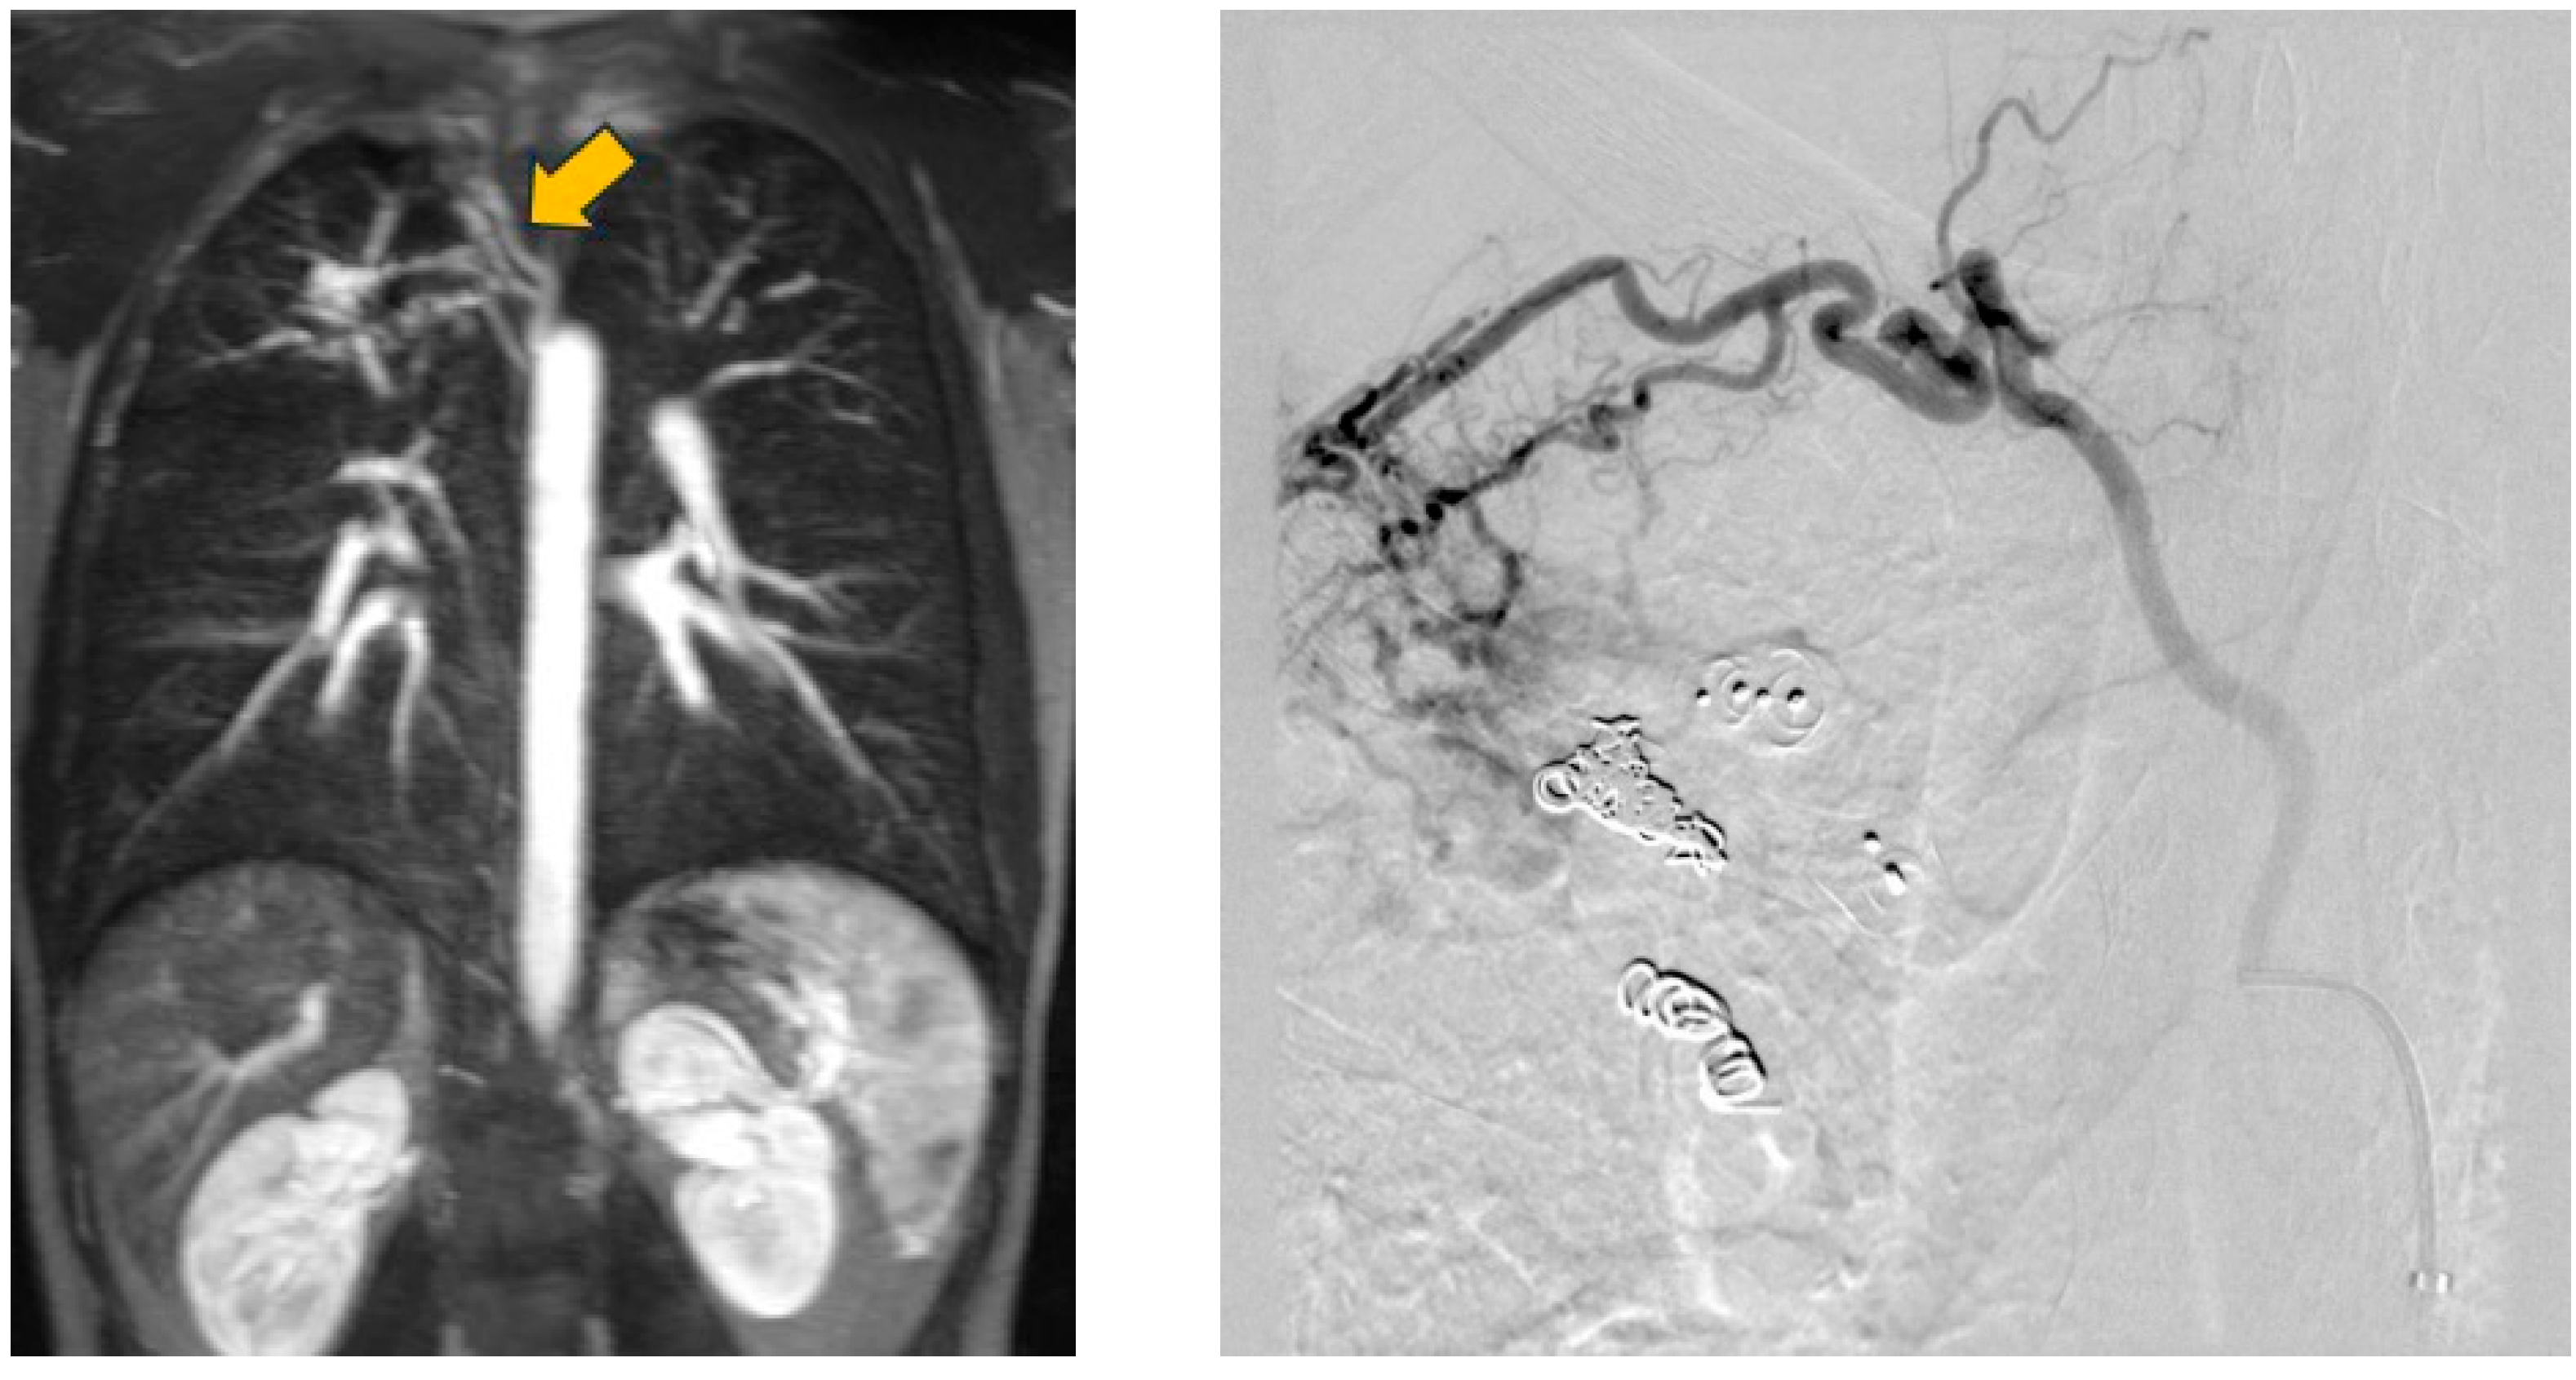

Furthermore, angiography images were examined for possible causes of reperfusion during re-embolization. In a total of 64 recanalized AV shunts, recanalization could be attributed to inadequate packing density of the implanted coils in 52 feeding arteries. Two examples are shown in Figure 7. In 15 of the 52 recanalized feeding arteries, we can further see a positioning of the embolization material on the wall of the vessel but not in the center (Figure 8).

The perfusion of PAVM was observed in two externally embolized malformations, which were initially embolized by detachable coils in the aneurysm sac. In another patient, reperfusion could be attributed to an increase in the size of the feeding artery. During the initial embolization at the age of four years, the diameter was 1.5 mm and seven years later a diameter of 2.1 mm was determined during re-embolization. In another patient, the dilatation of the feeding artery in the area of the implanted embolization material was observed. This was already seen in the MRA performed and confirmed in a subsequent angiography. Furthermore, the fixation of the implanted coils in the arterial wall was evident in the DSA series. Figure 9 shows both the screening and the angiography images, with the open arrow in the MRA image showing the dilation of the feeding artery and the white arrows in the DSA image indicating the fixation of the implanted coils. The white line also emphasizes the dilatation of the feeding artery. It should also be emphasized that the embolization material completely filled the feeding artery during initial therapy and that the complete occlusion of the vessel was achieved.

Figure 7. Presentation of two PAVM with insufficient packing density of implanted coils.

Figure 8. Presentation of two PAVM with spiral creation of implanted coils at the arterial wall.